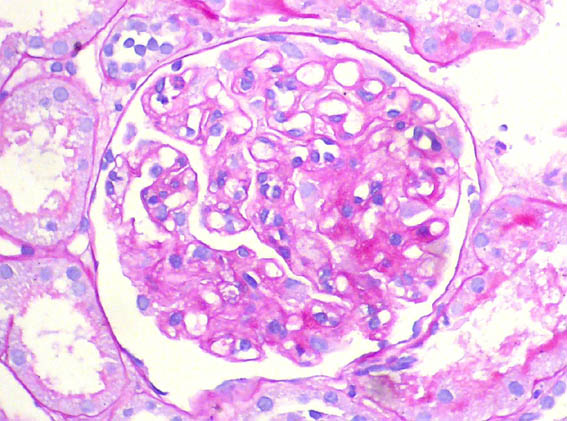

Figure 3. PAS, X400.

Figure 4. PAS, X400.